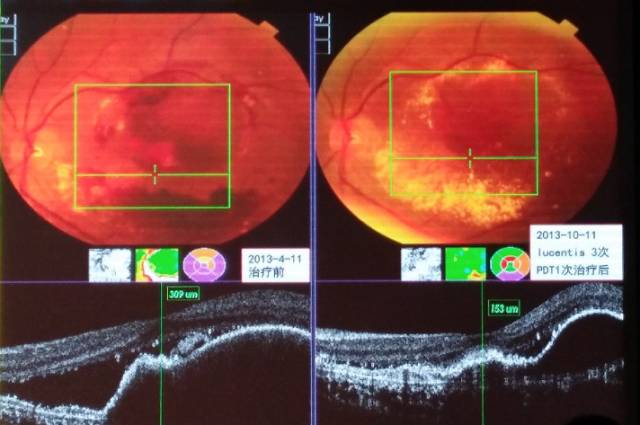

利器三:光动力疗法(photodynamic therapy, PDT)

光动力疗法是在光敏剂的引导下,通过一种特殊的非热能激光照射,破坏黄斑部异常的新生血管,从而减少黄斑区病变组织的出血、水肿和渗出,稳定患者视力,提高患者生活质量,是一种目前国内外公认的治疗黄斑脉络膜新生血管(CNV)的安全有效微创的新技术。PDT主要用于治疗湿性黄斑变性、病理性近视合并黄斑病变、中心性渗出性视网膜病变、中心性浆液性视网膜脉络膜病变等黄斑部新生血管疾病。针对某些对抗VEGF药物治疗反应迟缓或者耐受的CNV患者,可联合或者更改为PDT治疗,往往会取得一些令人满意的治疗效果(见图12)。

图12. 息肉样脉络膜血管病变抗VEGF联合PDT治疗前后眼底和OCT对比图